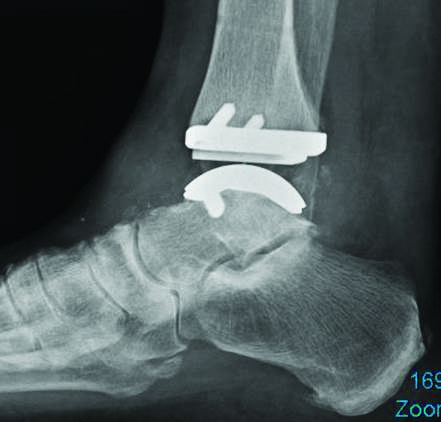

Endoproteza stawu skokowego

Do niedawna podstawowym leczeniem w przypadku zaawansowanych zwyrodnień stawu skokowego było jego całkowite usztywnienie (artrodeza). Od kilkunastu lat jednak coraz większą popularność zyskuje zabieg wymiany (endoprotezoplastyki) stawu skokowego. Proteza stawu skokowego przeszła liczne ewolucje i wchodzimy w fazę gdy zabiegi te odznaczają się wysoką skutecznością i bezpieczeństwem, a implanty są dobrze zaprojektowane i wykonane z najwyższej jakości materiałów.